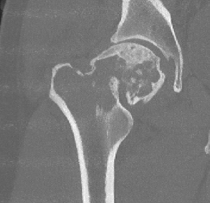

CT

Lytic lesion with punctate or spotty calcification

- endosteal scalloping is hallmark of chondrosarcoma

Large calcification with endosteal scalloping humerus

Large calcified lesion with endosteal scalloping